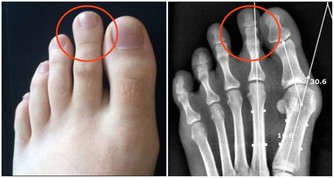

不伴有腎病或痛風的高血壓病人,可多吃大豆、花生、黑木耳、或白木耳以及水果。